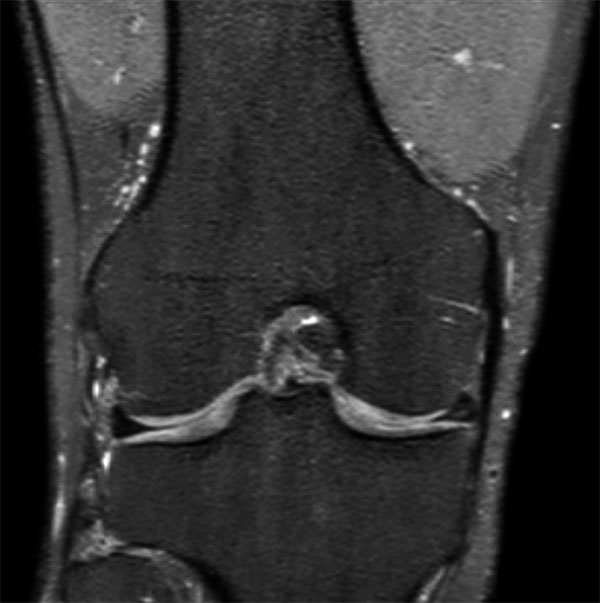

Comprehensive 3D knee imaging with MSK VIEW